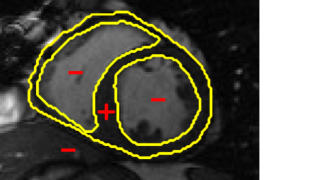

In cardiac image analysis, there are multiple structures (the right and left ventricles, and myocardium) that all useful and should be segmented. Our method is easily adaptable to this case. Indeed, computation of in Section III-C can be readily generalized. In general, multiple level sets should be used to represent multiple regions. However, in our case of interest (ventricles and surrounding epicardium), the regions form a rather simple topology (see Figure 3), and all regions can be represented using a single level set.

V-B Ventricle Segmentation: Comparison of Three Registration Schemes

In this experiment, we focus on real cardiac MRI data and compare registration methods used for segmentation of the LV and RV. We visually compare the tracking results given by our method to (M1) registration of only the interior of current estimate of the ventricle to a subset of next image (to show whole image registration is needed), and to (M2) standard full image registration with global smoothness. M1 is achieved by computing just the inside velocity with Neumann boundary conditions on (normal constraint does not apply in M1). The best results with respect to ground truth are chosen by choosing the optimal parameter in all methods. Results on LV and RV tracking for a full cardiac cycle are given in Figure 6 for the LV and Figure 7 for the RV. Registering only the organ (M1) results in errors (as the background registration is helpful in restricting undesirable registrations of the foreground). Globally smooth registration (M2) smooths motion from irrelevant background structures into the ventricles, which results in drifting from the desired boundary. Our method, which smooths within regions with satisfying the physical constraint, is able to achieve the most accurate results.